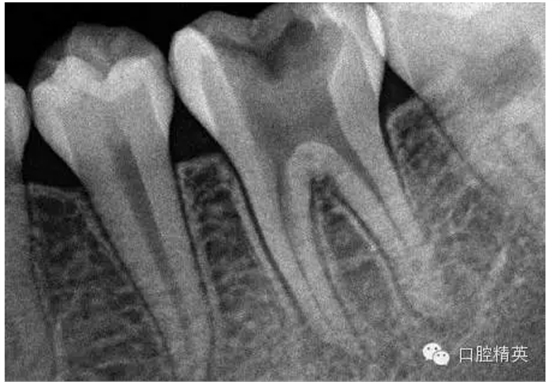

1,術(shù)前X-ray,常規(guī)術(shù)前攝片,

為患者和自己保留一份客觀記錄。。。

3,術(shù)前左下6近中根管斷針X-P,斷針長度約4MM,根尖慢性炎癥影像。。。